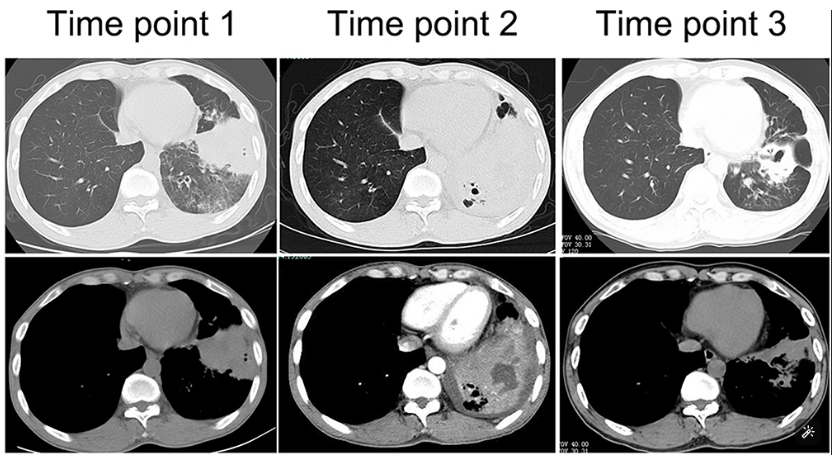

由于厌氧菌培养非常困难,既往我们对厌氧菌的认知仅限于在消化道定植,对其致病机制以及何种情况下致病并不非常清楚。厌氧菌定植于皮肤黏膜,是一种内源性微生物,感染发生率高,可导致严重、致死性感染。由于标本采集和转运的特殊性,使厌氧菌难以分离;加之其培养困难,体外生长慢,所以既往很难识别。厌氧菌在治疗方面存在一定挑战,如往往混合多重感染,且易产生耐药,也会因治疗延迟导致治疗失败。随着近10年来NGS技术的应用和普及,我们对厌氧菌的认识得以提升。常见的致病厌氧菌分为革兰阳性球菌、革兰阴性球菌、革兰阳性非芽孢杆菌、革兰阳性芽孢杆菌以及革兰阴性杆菌(表1)。革兰阳性非芽孢杆菌中可能致病的是放线菌,例如龋齿放线菌参与龋齿的发病过程。革兰阳性芽孢杆菌往往具有致病性,其中产气荚膜杆菌、艰难梭菌/难辨梭状芽孢杆菌、肉毒杆菌/肉毒梭菌、破伤风梭菌/杆菌具有强致病性。革兰阴性杆菌中的拟杆菌属对青霉素类药物具有很强的耐药性,易致青霉素治疗失败。临床中我们与厌氧菌的接触逐渐增多,对其特点也会愈发熟悉,对于临床诊断和治疗也会有所帮助。在NGS报告中通常会将检出的厌氧菌列为“C类”,定义为致病性C类—呼吸道正常微生态菌群,一般不导致感染。但当患者存在误吸风险时,需关注厌氧菌引起肺脓肿的可能。此时就需要针对患者的危险因素、临床表现、影像学、病原学以及气管镜下特点等进行综合分析。微小单胞菌最早是通过培养进行鉴定。瑞士2015—2022年132例病例报告的培养鉴定结果显示,血液中检出微小单胞菌37例(28%),肺内(肺脓肿、脓胸)检出29例(22%),总体病死率较低(5.3%)。国内周华教授团队开展的一项回顾性研究分析了2019年1月至2020年7月经病理活检和mNGS诊断的5例与微小单胞菌相关的慢性肺脓肿患者。患者的平均病程为6.5个月,共同特征是口腔卫生差,有酗酒史,且CT表现为边界不规则的高密度团块状实变影,并且在病灶中间可见液化性坏死,但没有发现气液平面或空腔,所以前期易被误诊为肺癌。下图1是该研究报告中病例3的肺部CT表现。时间点1:首次就诊时,左下叶可见团块状肺不张,伴周围磨玻璃样渗出病变,中心坏死不明显,可见细小空气囊泡影。时间点2:发病8个月时,可见大面积肺实变,增强CT示病灶内有液化坏死和小空洞。时间点3:经过3个月的有效抗厌氧菌治疗,病灶明显缩小,遗留空洞和纤维增殖病灶。图2是病例4的肺部CT表现。时间点1:患者首次就诊时,右上叶可见肿块样肺部实变影。时间点2:发病8个月时增强CT,可见实变明显增大,病灶内出现液化坏死。时间点3:经过3个月的有效治疗,病灶明显缩小,有残留空洞和纤维瘢痕样病变。由于通过影像学鉴别该病与肺癌具有挑战性,所以5例患者都接受了支气管镜检查和CT引导下经皮肺活检。5例患者经组织活检或支气管肺泡灌洗液(BALF)标本mNGS检测到微小单胞菌。病例: 女性, 67岁, 主诉"咳嗽咳痰2个月"。现病史:2个月前,患者家属感染新冠病毒(家属新冠抗原阳性)之后,患者出现咳嗽咳黄脓痰,无痰中带血及痰液拉丝,痰无臭味,无胸闷气短及胸痛,无咽痛咽痒,无鼻塞流涕。6月9日于当地市医院住院,住院期间出现发热,体温最高38.6℃,无寒战,查新冠病毒核酸阳性,予先诺特韦/利托那韦片口服治疗。查胸部CT见左肺上叶软组织影,左肺上叶炎症。诊断肺脓肿,予头孢唑肟联合莫西沙星,治疗后复查胸部CT(6月26日)病灶较6月9日明显吸收好转。6月14日气管镜检査见左肺上叶支气管开口狭窄,见大量脓性痰液堵塞支气管开口(病原学结果家属无法提供)。6月30日办理出院后仍有咳黄脓痰,无发热畏寒,口服止咳化痰药物,未使用抗生素。7月30日复诊胸部CT见左肺上叶异常密度较前增大。8月2日再次于当地市人民医院住院。8月4日气管镜检查: 左肺上叶黏膜肿胀肥厚, 管腔狭窄, 见大量白色干酪样分泌物涌出, 支气管镜不能进入。内科予莫西沙星静滴治疗10天, 外科予莫西沙星联合哌拉西林他唑巴坦静滴9天。复查胸部CT见病灶较前进展, 且右肺出现新发感染病灶。病程中患者饮食可, 睡眠差, 二便正常, 体重减轻5 kg。既往对阿莫西林过敏, 表现为口服阿莫西林后全身皮疹。否认嗜酒史及吸烟史。入院后胸部增强CT可见病灶内液化坏死,同时伴有小的空气囊泡影(图3)。患者有胸痛症状。气管镜检查发现气道内有痰栓或黏液栓阻塞征象(图4)。灌洗液tNGS结果回示:微小单胞菌(序列数2762),巨细胞病毒(序列数171),副流感病毒(序列数79),EB病毒(序列数61)。考虑病毒不会导致气道内如此改变,但由于微小单胞菌属于常见口腔定植菌,此时也不能完全确定微小单胞菌是否为引起感染的主要责任病原体。8月24日起予莫西沙星0.4 g qd ivgtt+哌拉西林他唑巴坦4.5 g q8h ivgtt。经过上述治疗,患者局部病灶有所吸收,但整个肺叶并无明显改善(图5)。气管镜检查仍然发现气道内有较黏稠的黏液栓阻塞气道开口(图6)。治疗经过:气管镜下予以局部冲洗,再次送检tNGS。9月7日结果回示:微小单胞菌(序列数6464),较前明显增多;副流感病毒(序列数998),EB病毒(序列数331)。9月9日起调整治疗方案为美罗培南1 g q8h。9月12日复查患者胸部CT,可见肺通气部分改善,肺组织内实变较前吸收(图7)。第三次气管镜检查仍可见少量痰栓嵌塞在远端支气管开口(图8)。患者此后转入医联体医院继续抗感染治疗。病例2:女性,54岁。主诉:咳嗽咳痰2个月,发热1周。现病史:入院2个月前,患者在西南地区旅游时感冒,出现咳嗽咳痰,白痰为主,量多,无胸痛,无发热,无痰中带血,咳时气短。于河北某诊所间断输液治疗14天(具体不详),期间口服中药治疗,症状未缓解。入院3周前(2023-09-07)就诊于当地县医院,查胸部CT提示右肺炎症,静脉滴注氨曲南、左氧氟沙星、氨溴索治疗1周,症状未缓解。2023年9月14日复查胸部CT显示右肺炎症较前加重,于当地中心医院住院。动脉血气分析:pH 7.43,PaCO2 38.4 mmHg,PaO2 67 mmHg,SaO2 94.2%;血沉90 mm/h;生化:白蛋白35.3 g/L;CRP 82.7 mg/L;血常规:WBC 9.75×109/L,NEU 6.83×109/L,HGB 104 g/L。静脉滴注莫西沙星。入院10天前,行肺穿刺活检,病理回报为少量肺组织及纤维结缔组织,炭末沉积,较多中性白粒细胞、淋巴细胞及浆细胞浸润,伴脓肿形成;肺穿刺mNGS结果回报:微小单孢菌(序列数2650),鲍曼不动杆菌(序列数17),人类疱疹病毒4型(序列数60),人类疱疹病毒7型(序列数5),文氏密螺旋体(序列数4337),解卵磷脂密螺旋体(序列数1121),齿垢密螺旋体(序列数698)。调整抗生素为头孢哌酮舒巴坦2 g q12h。入院1周前,出现发热,体温最高38.5℃,不伴寒战,咳嗽咳痰无加重,无咯血;复查血常规、PCT、CRP均明显增高(未见报告单);复查胸部X线提示右肺炎症范围增大,右侧胸腔积液。更换抗生素为哌拉西林他唑巴坦4.5 g q8h。4天前,支气管镜下见右肺下叶背段支气管略狭窄,黏膜水肿,可见脓性分泌物溢出。BALF革兰染色查见革兰阴性杆菌,抗酸染色、霉菌未见异常,培养未回报。患者体温逐渐降至正常,咳嗽咳痰有所减轻,复查胸部CT提示右肺高密度影,右侧胸腔积液较前增多。为求进一步诊治来我院就诊被收入院。既往甲状腺功能减退病史5年,目前口服优甲乐治疗,监测甲状腺功能指标在正常范围。20年前因宫外孕行手术治疗。2023年10月8日胸部CT示胸膜下斑片状坏死,纵隔窗可见微小空气囊泡影及密度不均匀液化坏死(图9)。治疗:9月28日至10月13日莫西沙星0.4 g qd ivgtt+哌拉西林他唑巴坦钠4.5 g q8h ivgtt。最终患者病灶吸收好转并顺利出院。患者男性,42岁。主因间断咳嗽、咳痰1月余,左侧胸痛、气短2天入院。现病史:入院前1月余(2022-07-19),患者无明显诱因出现咳嗽,咳白痰,痰中有少量鲜红色血丝,左侧胸痛(为钝痛),深吸气后加重,就诊于当地医院。完善肺动脉CTPA:示左上肺动脉舌段分支局部管腔可见线条样低密度充盈缺损,考虑肺栓塞;左肺上叶实性病变伴不均匀强化,性质待定,部分为肺梗死改变可能,纵隔多发稍大淋巴结,性质待定;右肺下叶后基底段可见一不规则实性结节,边缘可见多发毛刺,直径约0.7 cm。当地医院考虑肺栓塞不除外,肺部感染?右肺下叶结节,予莫西沙星抗感染,低分子肝素抗凝,乙酰半胱氨酸化痰。完善CT引导下肺穿刺活检,病理示:肺泡腔扩张伴上皮轻度增生,肺泡间隔纤维组织增生伴散在炎细胞浸润,未见恶性病变。院外规律应用甲磺酸艾多沙班60 mg bid抗凝,先后间断应用左氧氟沙星0.5 g qd、头孢类抗生素(具体药物、剂量不详)抗感染。患者仍有间渐咳黄白痰,量不多,痰中有少量鲜红色血丝;无畏寒、发热、胸痛、夜间阵发性呼吸困难症状,无尿少、双下肢水肿,无口干、咽干,无牙齿成片脱落,无晨僵、关节肿痛,周身无皮疹,无盗汗乏力。2天前(2022-09-16)患者无明显诱因再次出现左侧胸痛,疼痛剧烈,深吸气、咳嗽及改变体位时加重,伴气短,就诊于我院急诊。完善肺动脉CTPA:肺动脉主干及其各叶段分支未见明显充盈缺损,左肺上叶舌段团块影,最大截面约7.6 cm×5.3 cm,边界不清,周围可见晕征;增强扫描不均匀强化,邻近胸膜增厚,性质待定,建议穿刺活检;纵隔及左肺门多发淋巴结显影。血细胞分析:WBC 11.09×109/L,NEU% 80.8%,NEU 8.95×109/L;CRP 54 mg/L,PCT 0.07 ng/ml。患者自发病以来,精神状、食欲及睡眠均一般,大小便正常,体重下降5 kg。2022年9月14日外院胸部增强CT:胸膜下楔形的影像学表现可见少量小气泡囊以及液化坏死病灶(图10)。初始考虑肺部肿瘤及肺栓塞。经过初步抗感染及抗凝治疗,患者病情无缓解,2022年9月27日患者突发胸痛,下肺影像加重并且出现脓胸(图11)。行胸腔穿刺并将脓液送检mNGS,结果回报:牙龈卟啉单胞菌(序列数3)。尽管序列数很低,但考虑是脓肿穿刺结果,因此考虑该菌致病可能。抗厌氧菌治疗:9月16-28日莫西沙星0.4 g qd ivgtt,9月23日-10月12日美罗培南1 g q12h ivgtt,9月28日-10月8日万古霉素1 g q12h ivgtt,10月13-18日莫西沙星0.4 g qd ivgtt+甲硝唑0.5 g tid ivgtt。患者肺脓肿的整体治疗时间约为3个月,病灶逐渐吸收,最终形成一些纤维索条影(图12,图13)。1年后复查病灶基本吸收(图14)。图14 1年后复查胸部CT(2023-08-08)微小单胞菌和卟啉单胞菌这两种厌氧菌在临床中需要引起重视,它们容易引起肺脓肿/脓胸。2024年国内学者Li Yao等在Diagn Microbiol Infect Dis 杂志发表了一篇牙髓卟啉单胞菌感染所致肺脓肿的病例报告,文章也提到在胸水或肺组织活检中,通过mNGS同时检出了微小单胞菌和卟啉单胞菌感染引起的肺脓肿。文章还回顾总结了既往发表的厌氧菌感染引起肺脓肿的病例,2010年报道的是1例脑脓肿患者,2019年报道1例脑炎患者,2022年报道1例脓胸伴呼吸衰竭患者。3例患者预后都比较好,可见厌氧菌亦可导致肺外多部位感染。对于厌氧菌所致肺脓肿的诊断及其引起的脓胸,目前的文献报道仍然较少,我们对它们的认知也有限,因此也提醒大家关注相关疾病的诊断和治疗。我们也已将本研究小组8例微小单胞菌所致肺脓肿的系列病例的研究结果发表(Front Cell Infect Microbiol, 2024, 14: 1416884),可供需要的同行参考。对于厌氧菌感染,我们需要提高警惕。厌氧菌往往在口咽部定植,其引起的脓肿/感染往往多为亚急性或慢性起病。患者通常有发热、胸痛症状,脓肿会逐渐进展。由于厌氧菌与人体本身是一种长期共生的关系,人体对厌氧菌的免疫识别可能处于较低的防御反应状态,所以会形成一个亚急性或慢性的发病过程。通常情况下,因厌氧菌的菌群发生了移位,从卫生条件不好的口腔扩展到相对无菌的肺内,同时开始增殖,由此可能导致感染。因此,对于酗酒以及口腔卫生非常差的人群,我们要重视对其风险因素和病史的排查。患者就诊时可能病情并不重,有胸痛或咯血,很容易误诊为肺部肿瘤,往往在这种情况下进行肺穿刺或气管镜检查,mNGS可以发现较大序列数的厌氧菌。但在mNGS检出厌氧菌后的诊断过程中又容易形成误判——究竟是致病菌,还是定植菌?此时结合患者其他病史和影像学特点(有脓肿/痰栓形成,微小空气气囊泡影),可能提示厌氧菌感染。然而,厌氧菌感染在病原学和影像学诊断方面仍然存在诸多困难,极易漏诊和误诊。微小单胞菌感染患者在气管镜下可以看到典型的脓性分泌物嵌塞气道,导致气道阻塞,也会造成远端气道和肺泡引流障碍。所以,及时处理气道内痰栓,改善引流,可能是使患者获得良好预后的关键。厌氧菌肺脓肿的吸收比较缓慢,抗感染的疗程也比较长,需要在后期诊疗过程中密切随访和观察患者对治疗的反应以及耐药等问题,及时调整治疗方案,适当延长疗程。